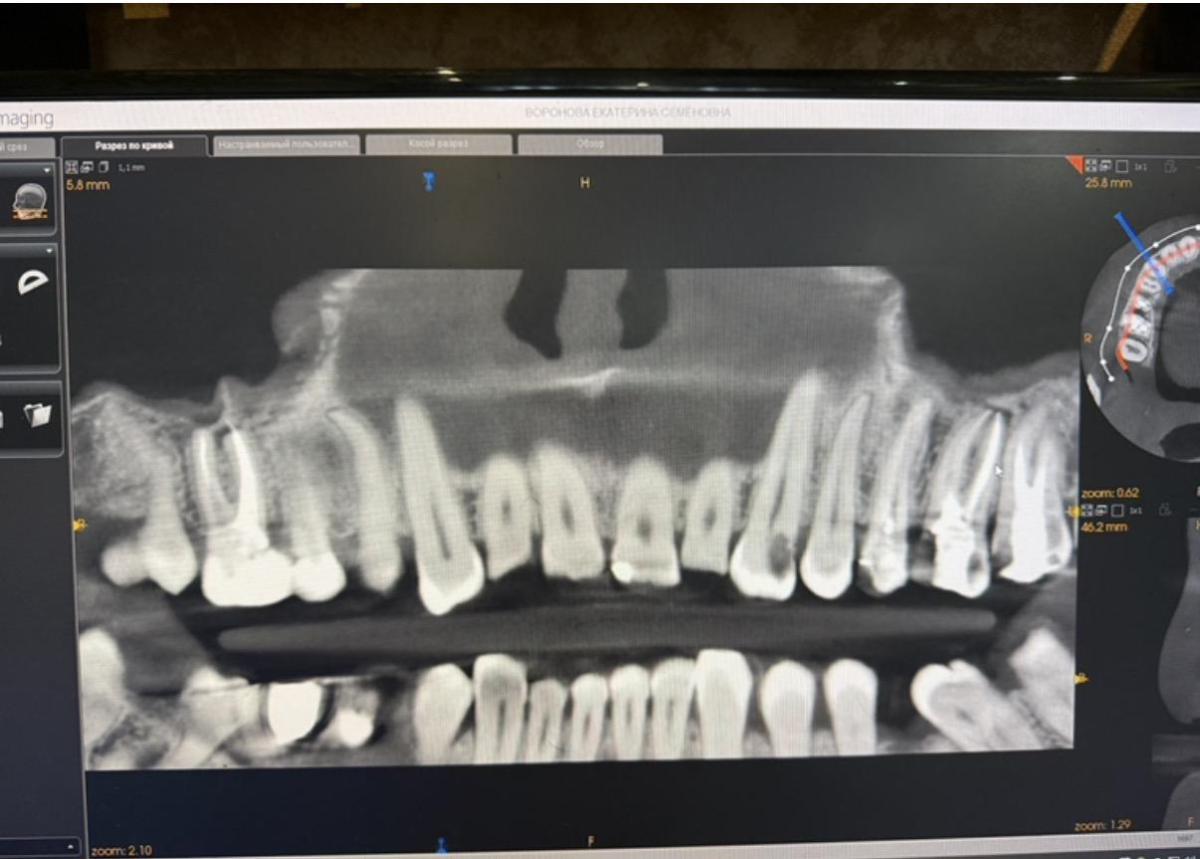

Юрий Жигурт, это снимок сделан 4.12.2025. Зубы 13,15,16,17,25,26 пролечены. До этого снимка, просто пломбы не фото. Имплант снизу справа тоже только в мае установлен, слева нет возможности это сделать, если только удалять своих два и устанавливать два имплантата. Не всегда все по снимку можно увидеть, надо и в реально смотреть.

Юрий Жигурт, видна разница, кт в год разница.